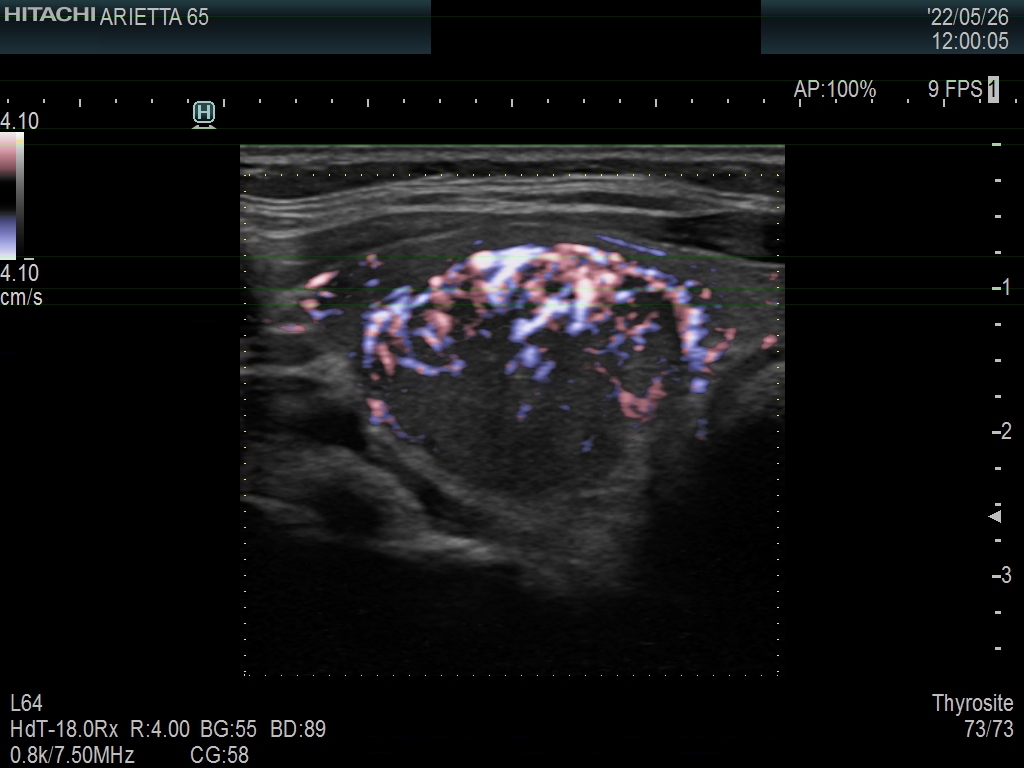

Ultrasonography. The thyroid was echonormal. There was a moderately hypoechoic nodule in the right lobe. The nodule has halo and presents with a combined perinodular and intranodular blood flow. The latter was irregularly increased.

The presentation of the nodule is not very suspicious. Halo sign is a rare finding in medullary cancers.

The classification of the nodule depends on the judgement of nodule borders. If it is regarded as irregular, then the lesion is an EU-TIRADS 5 one. However, if we judge the borders as non-lobulated, then the lesion is an EU-TIRADS 4 nodule. According to the EU-TIRADS, FNA is indicated in both cases because the largest diameter of the nodule exceeds 15 mm.